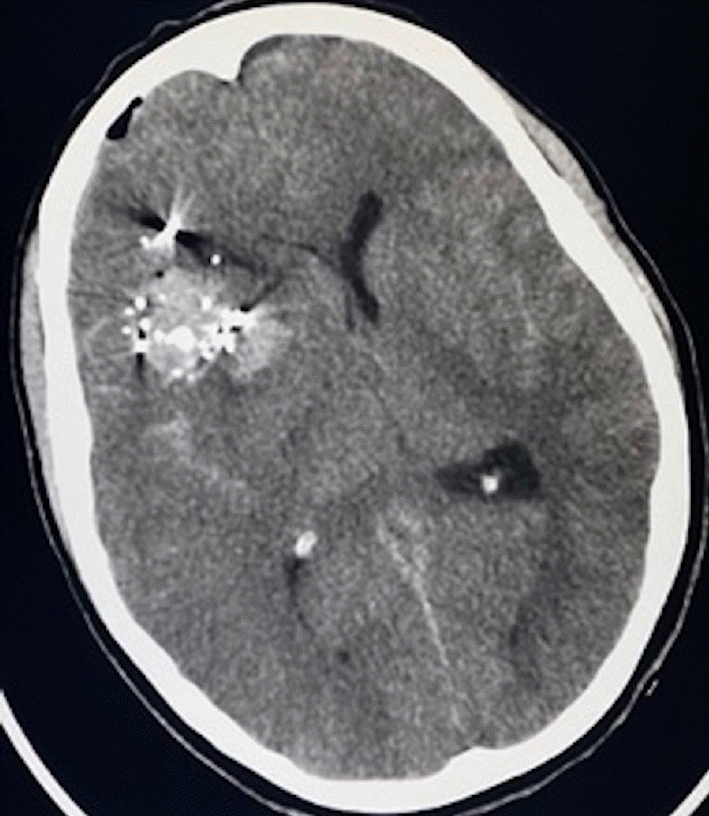

A woman in her third decade of life presented with severe penetrating brain injury secondary to cranial-facial gunshot wounds. Head computed tomography (CT) showed multiple calvarial and bullet fragments within the right frontotemporal lobes and a large right frontotemporal intraparenchymal hemorrhage with cerebral edema (Fig. 1). She underwent decompressive hemicraniectomy and evacuation of intraparenchymal hemorrhage and accessible bone and metal fragments.

Fig. 1.

Head CT demonstrating calvarial and bullet fragments in the right frontal lobe with large right frontal intraparenchymal hemorrhage associated with significant cerebral edema and midline shift. CT, computed tomography